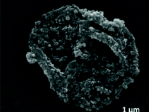

Air pollution particles and metals found in the placenta

Air pollution particles and metals found in the placenta23 September 2020

Pollution particles, including metals, have been found in the placentas of fifteen women in London, according to research led by Queen Mary University of London.